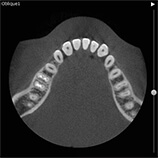

当クリニックでは歯科用CT装置を導入しています。

歯科用の3次元CTにより、いままで以上に詳細な診断ができるようになりました。

インプラント、歯周病、根管治療(歯の根の治療)、顎関節症などの治療時に有効です。

※CT画像一例